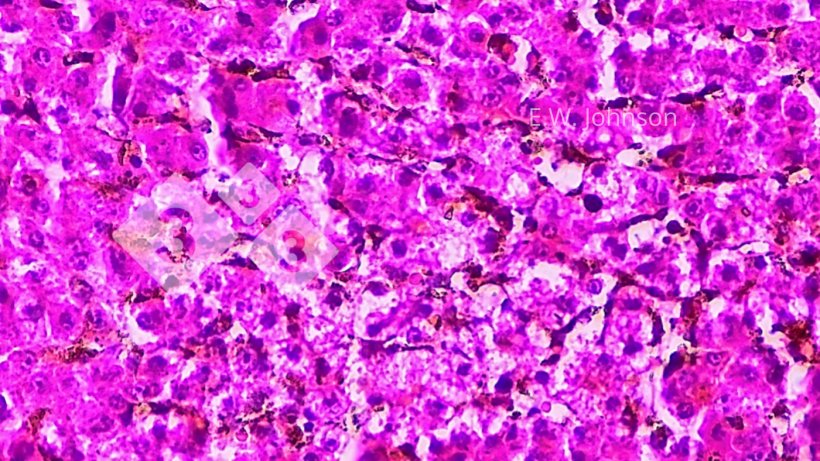

El examen microscópico del cerebro revela una meningoencefalitis con manguitos perivasculares y gliosis (imagen 2) e infiltración de las meninges con células inflamatorias mixtas mononucleares y polimorfonucleares (imagen 3).

Se observa necrosis focal en el hígado y cuerpos de inclusión intranucleares anfofílicos en el tejido que rodea las áreas de necrosis (imagen 4). Se realiza un diagnóstico presuntivo de Enfermedad de Aujeszky (EA).